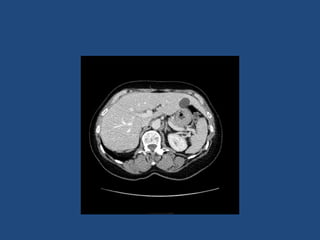

Imaging

• CT better at eliminating malignancy

(dedicated CT looking at Hounsfield units (HU)

and washout characteristics)

– <10HU = benign (sens 71%, spec 100%)

• MRI may characterise phaeos better

• FDG-PET good for phaeos and cancer

• FNA – consider if cancer history and >10HU on CT

after exclusion of phaeo

Imaging - size

• >4cm 90% sensitivity carcinomas

24% specificity (ie only 24% cancer)

• >6cm 25% chance of it being carcinoma

• <2cm + hypodense then unlikely to grow

• If change in size >1cm over 6 months consider

resection

Practical suggestion

• Most have not had dedicated CT (ie bottom of CT

chest or CT colon)

• If <4cm do dedicated adrenal CT 6 months after

presentation

– No need to rescan if no change in size (or <0.8cm)

• If >4cm do dedicated adrenal CT when referred to

get characteristics and consider repeat or MRI in a

further 6 months if looks benign

• <2cm and no change then discharge

2- 4cm monitor clinically for longer?

Imaging • CT betterat eliminating malignancy (dedicated CT looking at Hounsfield units (HU) and washout characteristics) – <10HU = benign (sens 71%, spec 100%) • MRI may characterise phaeos better • FDG-PET good for phaeos and cancer • FNA – consider if cancer history and >10HU on CT after exclusion of phaeo

Imaging - size •>4cm 90% sensitivity carcinomas 24% specificity (ie only 24% cancer) • >6cm 25% chance of it being carcinoma • <2cm + hypodense then unlikely to grow • If change in size >1cm over 6 months consider resection • Guidelines suggest: – NIH: 2 CTs 6M apart – Young et al + UptoDate: 0,6,12,24m – BES: Repeat image – increase in size of 0.8cm over 6-12M consider surgery

Practical suggestion • Mosthave not had dedicated CT (ie bottom of CT chest or CT colon) • If <4cm do dedicated adrenal CT 6 months after presentation – No need to rescan if no change in size (or <0.8cm) • If >4cm do dedicated adrenal CT when referred to get characteristics and consider repeat or MRI in a further 6 months if looks benign • <2cm and no change then discharge 2- 4cm monitor clinically for longer?